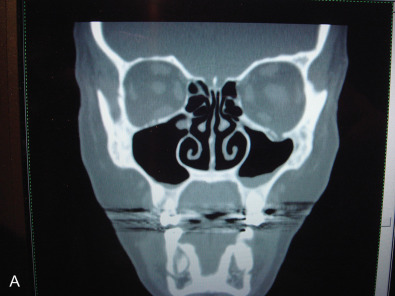

While the computed tomography (CT) scans usually cannot demonstrate nerves directly, the injury to a bone adjacent to the known anatomical location of a nerve supports the diagnosis of posttraumatic facial pain due to that nerve. This is demonstrated in Fig. 3.15.5A where the left orbital floor is lower than it is on the right, and the infraorbital canal is deformed on the left. In Fig. 3.15.5B , the right infraorbital nerve is injured at the location of the fixation plate at the infraorbital rim. Another example is given in Fig. 3.15.6 , where the right inferior alveolar nerve was injured twice; the first time with a screw designed to hold a bone graft prior to dental implant placement, and then a second time, when a metal clip was placed on the mental nerve at the mental foramen. The application of 3T MRI to the cranial nerves has brought a new dimension to being able to evaluate posttraumatic facial pain and is the best way to document vascular compression of the trigeminal ganglia and its roots.